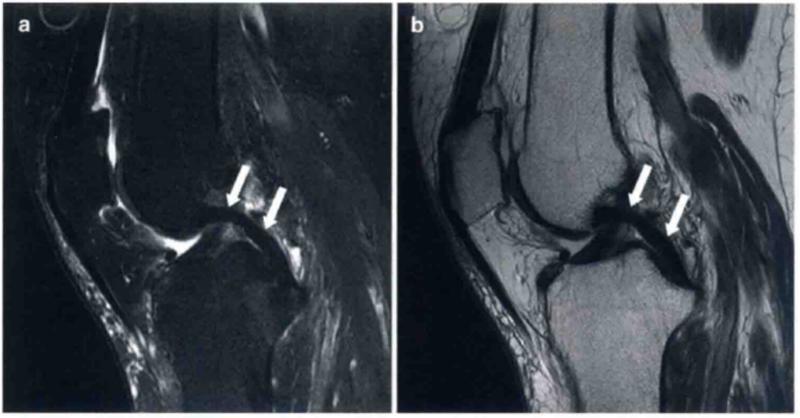

图4 a和b显示的为类似ACL损伤的表现。

a显示ACL完整,轻度松散黏液状降解(箭头)。a中ACL为增强的T2高信号,但是走行是正常的,没有不连续的病变,股骨附着点完整。b显示了完整的ACL和ACL腱鞘囊肿(箭头)